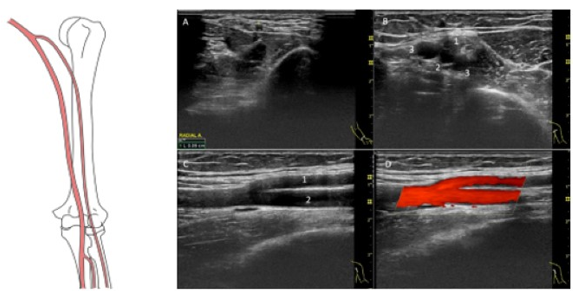

肱桡动脉变异导致AVF无法成熟

男性,49岁,糖尿病肾病CDK5期,建立左腕部RC-AVF,术后5个月通路震颤微弱,无法使用

超声提示左上臂肱动脉高分又变异,变异类型:肱桡动脉

处理:新建肘部MCV-BRA AVF